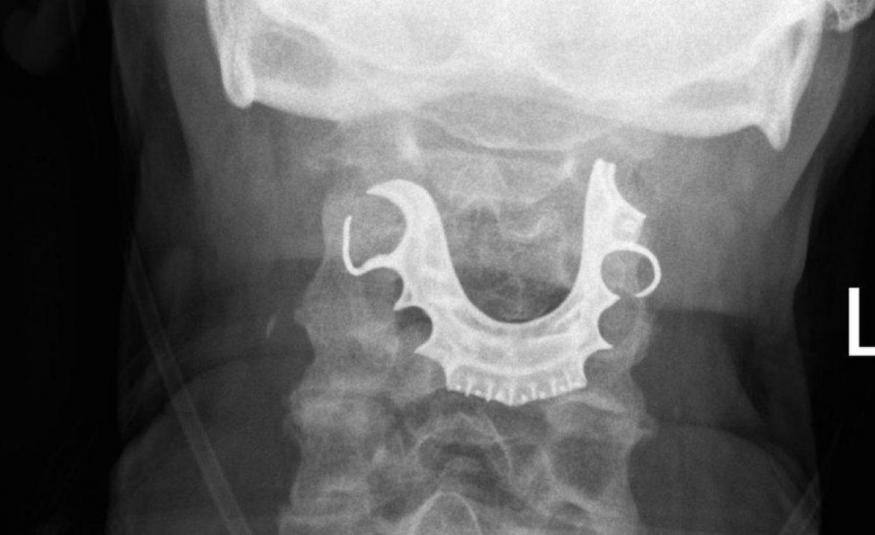

Proteza nađena u grlu muškarca nakon operacije (FOTO)